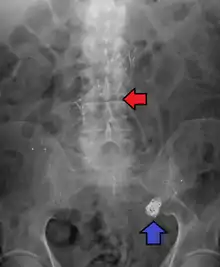

![]() | |

| Angiography of an aneurysm in a brain artery. The aneurysm is the large bulge in the center of the image. | |